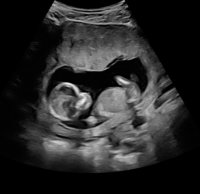

15 uker + 1 eller 2 dager, 120 g, 10 cm

Aktiv liten frisk baby som sprellet og snudde seg rett som det var! Hun var usikker, men mest sannsynlig er det en liten gutt. En måned til OUL og (kanskje) en endelig bekreftelse på det bildet ble sidelengs her, men SE! Det er jo et lite miniatyrmenneske inni der!